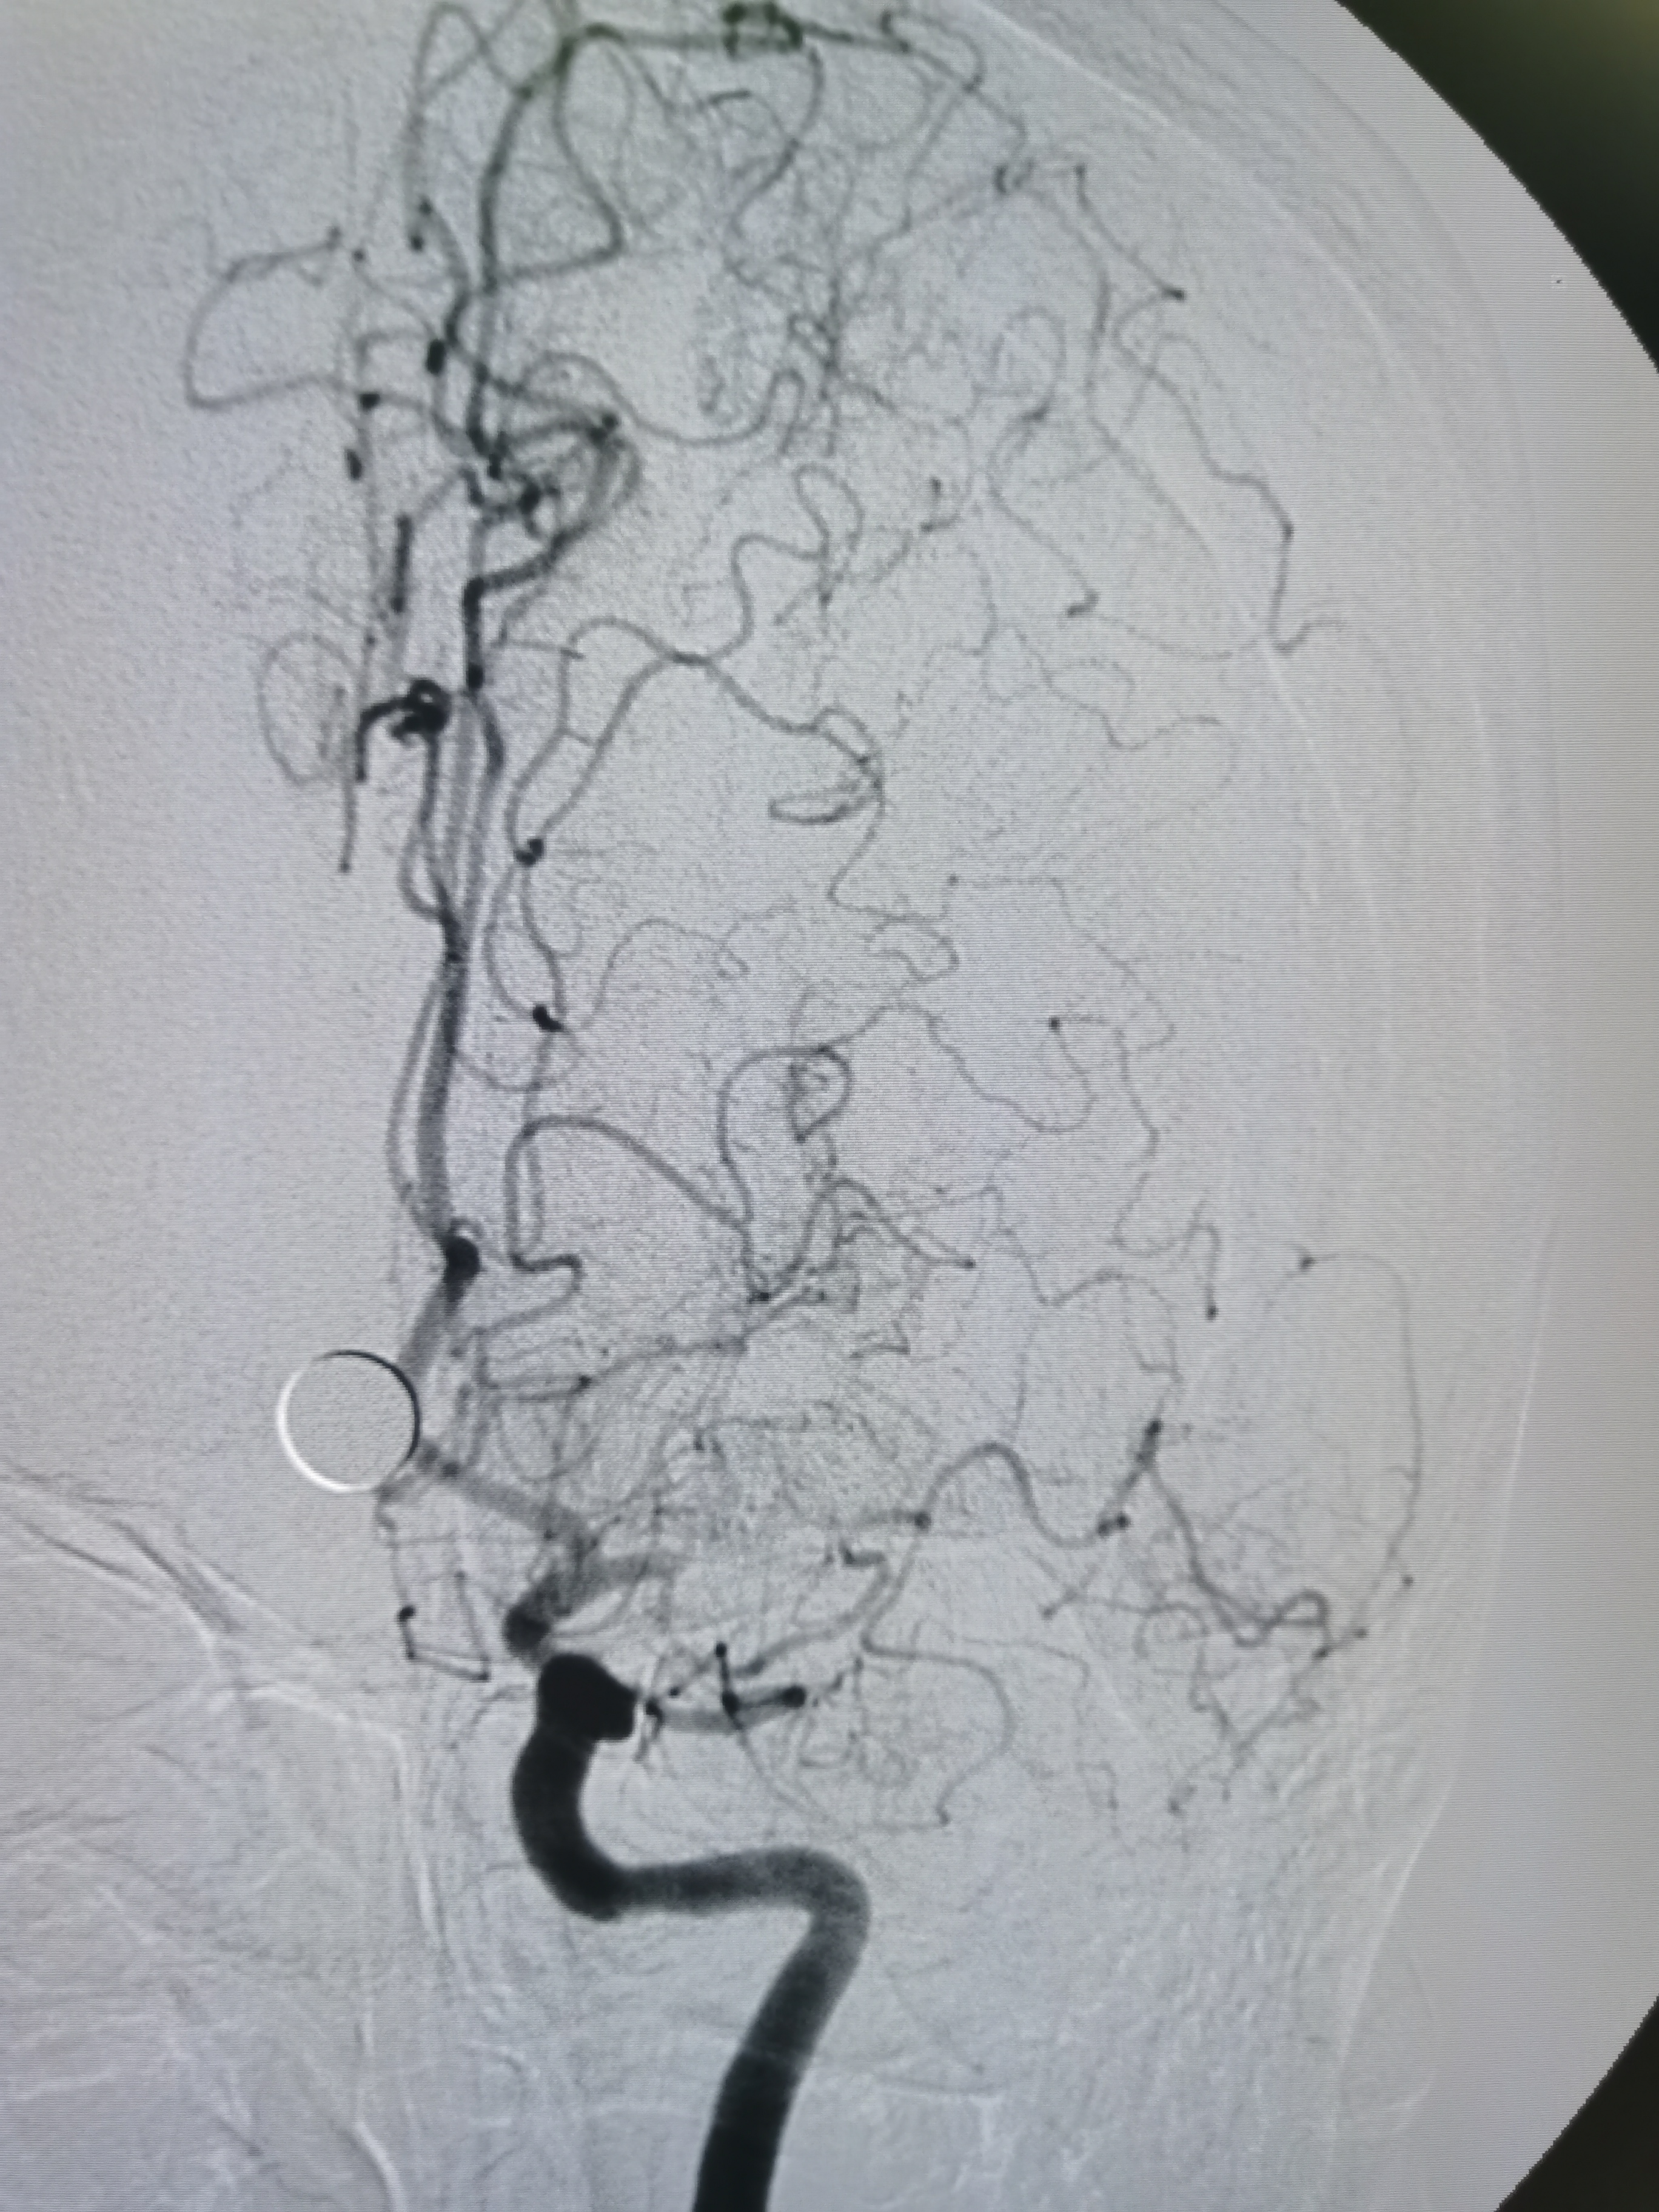

侧位见左侧大脑中动脉闭塞。

晚期可见左侧大脑中动脉返流。

正位见左侧大脑中动脉闭塞。

动脉晚期可见左侧大脑中动脉M2段返流。

造影分析:

患者左侧大脑中动脉M1起始段闭塞,动脉晚期可见返流至M2显影,考虑新近闭塞,具备介入开通指征,手术风险在于血管夹层,破裂及急性血栓形成,向患者家属详细交代病情后,家属积极要求介入治疗。